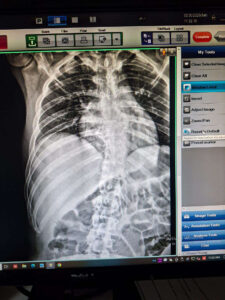

Rivière Ryan Bradley, 22 ans, souffre d’une fracture par compression T7 et T8 et est paraplégique. Financièrement, son traitement, ses billets d’avion et son hébergement coûteront Rs 634 275 .